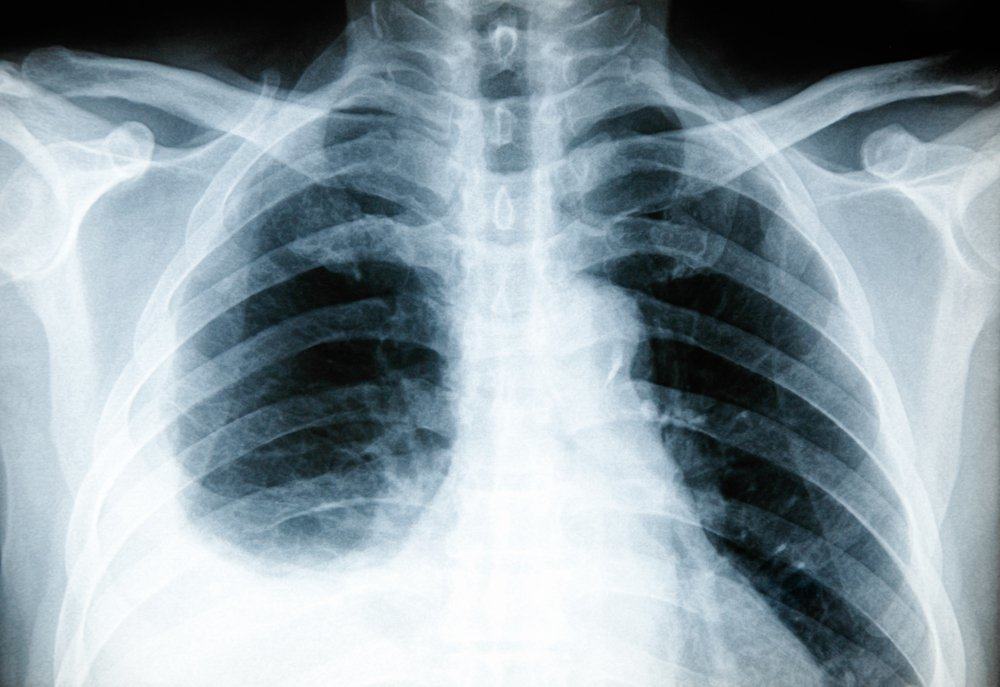

1. X-ray dada

Tes x-ray di bagian dada dapat membantu dokter mengetahui adanya peradangan pada paru-paru Anda. Jenis x-ray yang dilakukan adalah dekubitus, yaitu x-ray yang diambil ketika Anda berbaring dengan posisi miring.

Dengan posisi ini, penumpukan cairan yang terdapat di pleura Anda dapat terlihat secara lebih jelas.